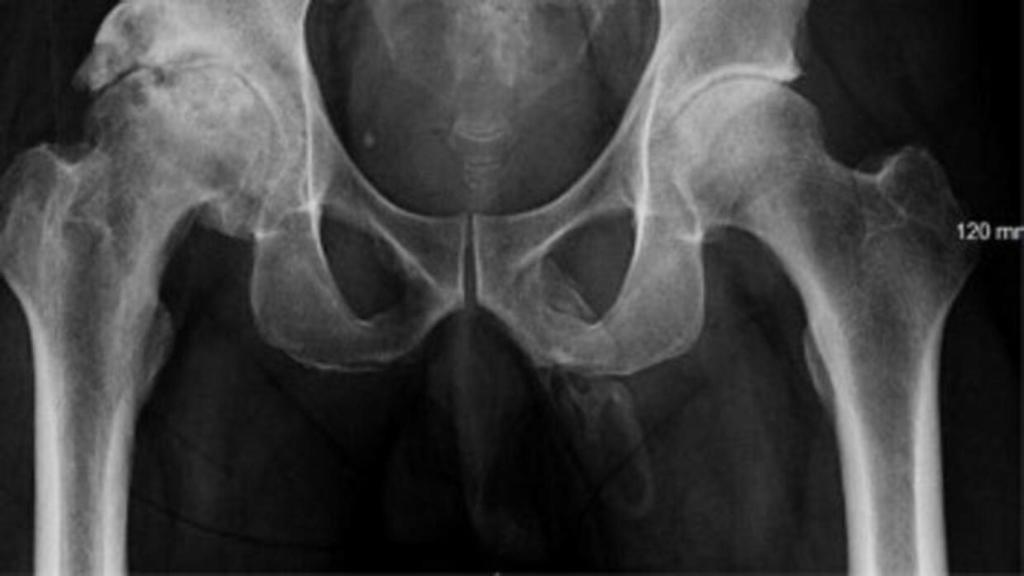

Radiografía en la que se aprecia la forma de un pene.

Un pene de hueso, un hallazgo casual

Según datos del informe del caso, publicado en la revista Urology Case Reports, la radiografía se realizó para descartar fracturas de pelvis o cadera, dado que la contusión tras la caída se había sufrido en dicha zona. Pero, sin embargo, lo que se detectó fue "una calcificación extensa, similar a la densidad hueso, a lo largo de la distribución donde debía estar el pene". En otras palabras, la sospecha inicial fue una "osificación del pene" o bien que el pene del paciente se había transformado en hueso.